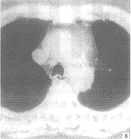

图4 女,16岁。两叶胸腺夹角成锐角,成箭头状,左外缘略弧形外凸

形态:胸腺分左右两叶,多不对称,整个胸腺呈上窄下宽的三角形。96%患者胸腺CT扫描很少见到两叶之间的结缔组织分隔,胸腺形态随年龄变化及其周围纵隔和肺结构大小、形态改变而改变,由方形或梯形(图3)逐渐呈新月形、烧杯形、箭头形(图4),其前缘可宽可窄,本组病例前缘最宽达5cm,最小呈线样。两外缘形态88%为内凹或平直,12%一侧外缘或两侧外缘呈弧形外凸,后缘不同程度伸沿到纵隔大血管间隙内呈波浪状。两叶胸腺长轴夹角78%呈锐角,22%呈钝角。

大小:如表1、2所示:随着年龄的增长,胸腺的宽、厚度、面积和随年龄增长而变化,各年龄组间统计学上无明显差别(P>0.05),除极少数例外,胸腺左叶通常大于右叶(图4)。随年龄增长,胸腺厚度范围5~30mm,平均值为9.72~13.92mm。胸腺宽度随年龄增长而呈增大趋势,以左叶更明显,最宽的1例,左叶宽68mm。其静脉弓层面测量两叶胸腺面积和不与年龄增长的成比例增大(表3),最大1例,胸腺面积为1785mm2。本组病例胸腺上下径40~90mm左右。